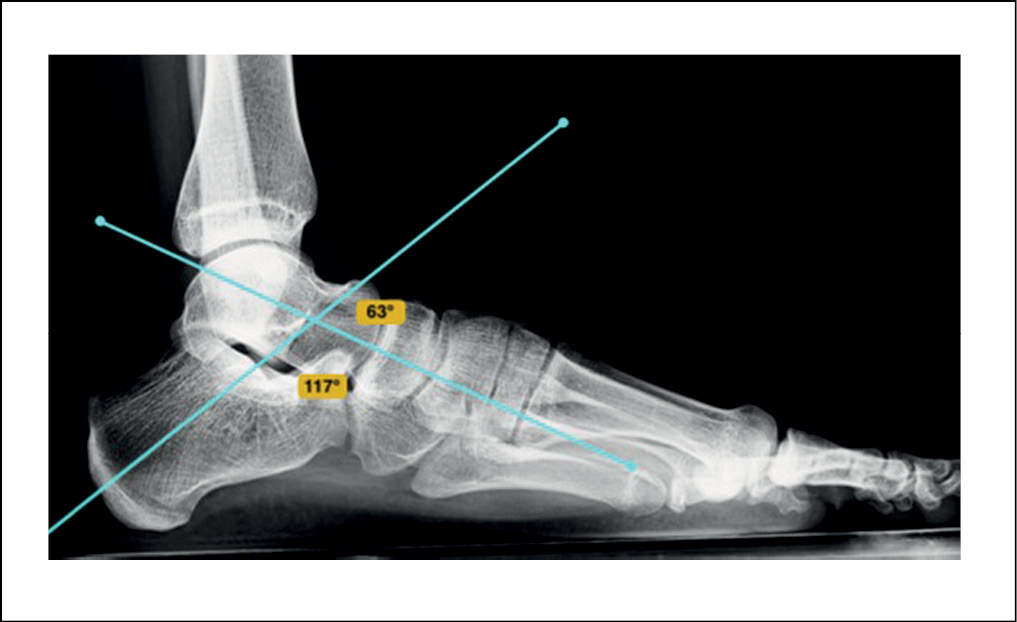

На контрольном осмотре отмечалась положительная динамика, проявляющаяся в виде полного отсутствия болевого синдрома на правой стопе, уменьшения выраженности болевых ощущений на левой стопе. Рентгенологические и фотоплантографические показатели были в пределах референтных значений данной возрастной группы. Показатели мануальных и функциональных тестов также улучшились (рисунки 6, 7).

Рисунок 7. Рентгенограмма левой стопы под нагрузкой после оперативного лечения. / Figure 7. X-ray of the left foot under load after surgical treatment.